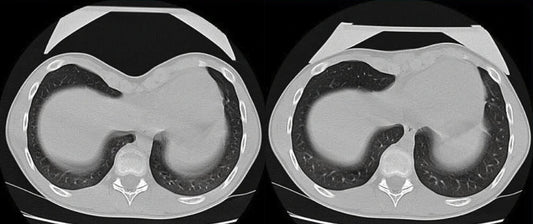

Below: Before and after Vacuum Bell treatment on a CT scan